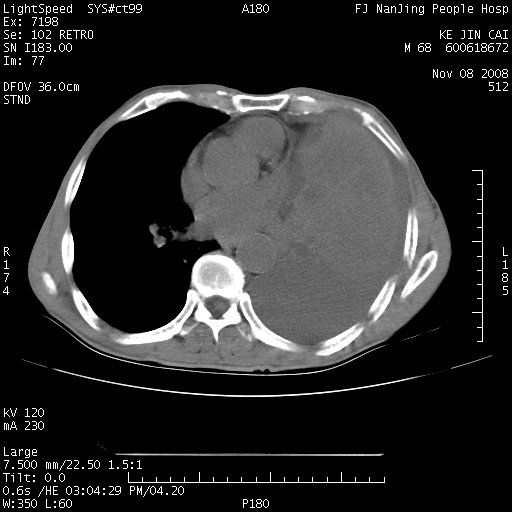

是个很有看头的病例,咋人气那么不旺?没多少人兴趣呢?这个病例几大怪:1   恶性肿瘤侵犯心肌左房怪,心肌一般不会被恶性肿瘤侵犯吧?2   左下肺均匀实变怪,内无含气,有别一般不张实变,含气肺泡完全为液体取代,而非一般不张实变的肺萎陷,冷不丁还以为是肿大的脾脏3   肿瘤本身怪,像tb肺不张4   这么有看头的病例没人气怪。呵呵。

追查病史,咳嗽,患者无发热,血象不高。据说2年前胸片检查怀疑肺ca曾行纤支镜检查,病理未见到癌细胞。无确切资料。

左肺恶性肿瘤侵犯肺动脉,左心房内瘤栓,胸膜转移。

左肺恶性肿瘤侵犯肺动脉,左心房内瘤栓,胸膜转移,少见,学习了。